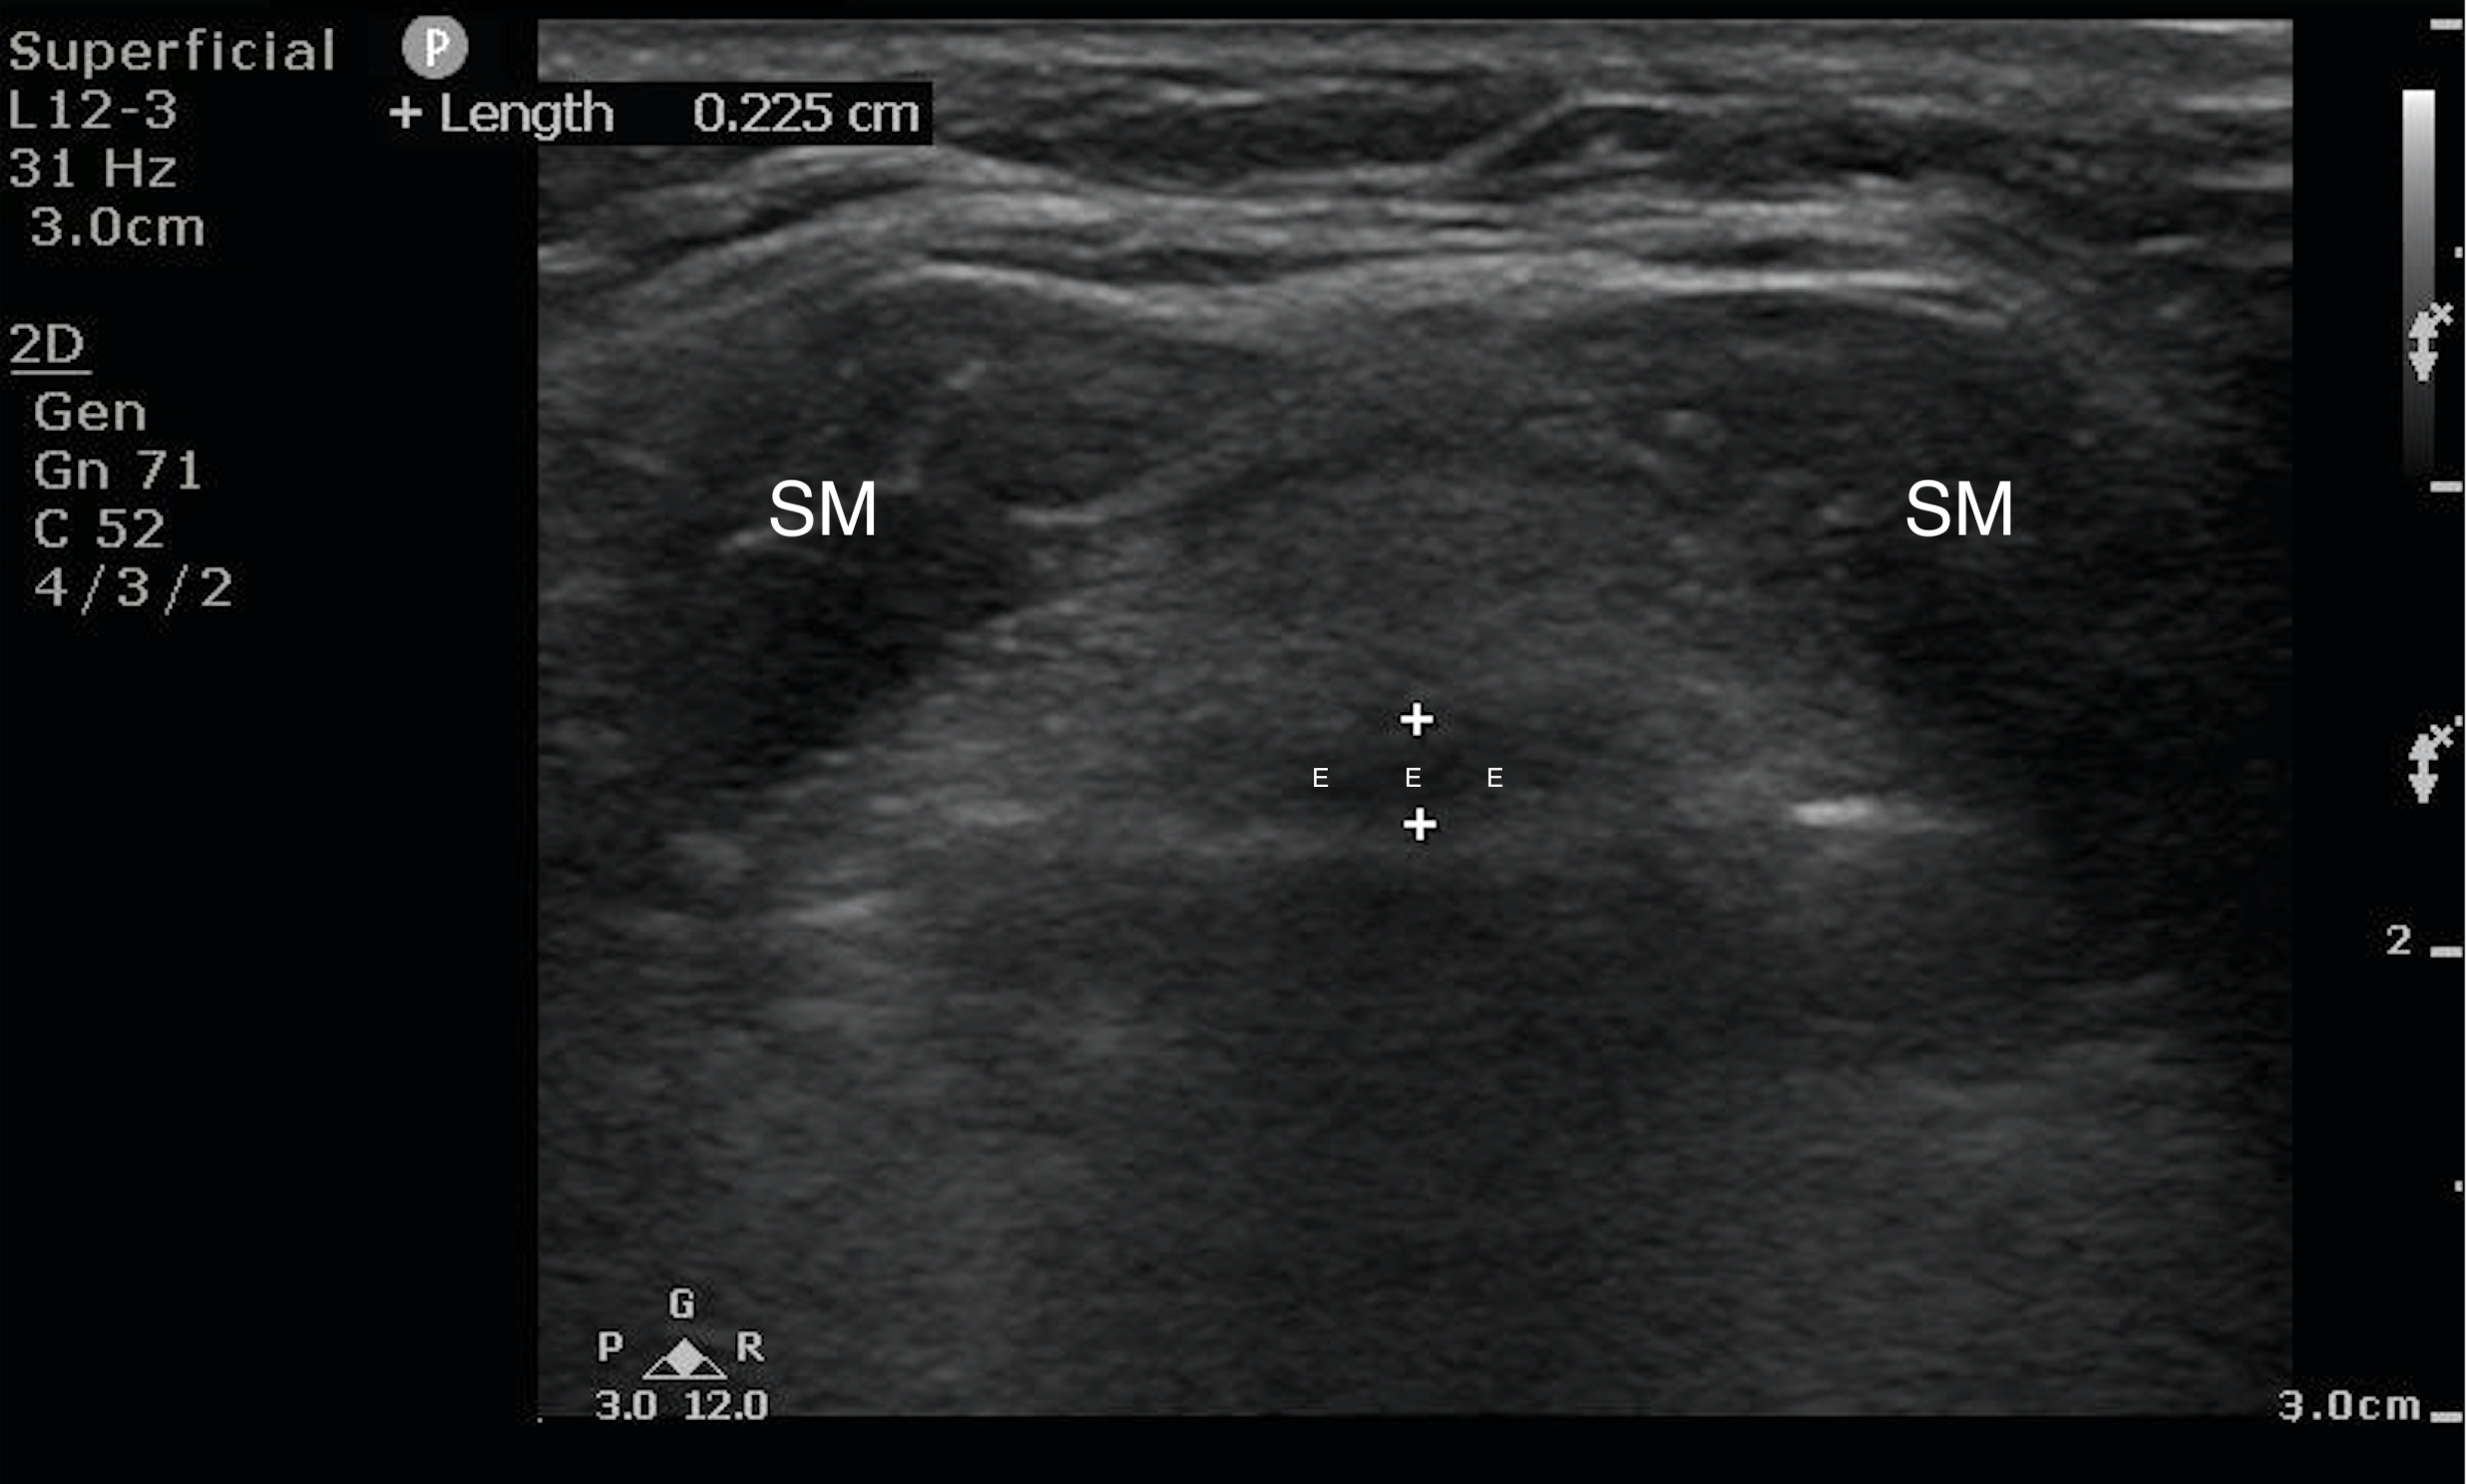

- Figure 3a and b. Step 3: Sliding down the neck ever so slightly and keeping the angle of the probe approximately the same as finding the hyoid bone, you will see a hypoechoic band in the far field with two circular hypoechoic structures in the near field, forming a frog face-like image. The hypoechoic band is the epiglottis (E) and the two circular structures are strap muscles (SM) of the neck. Normal thickness of the epiglottis in adults is <3mm. Far field to the epiglottis are hyperechoic artifacts due to air; the bright linear line is the air-mucosal interface.